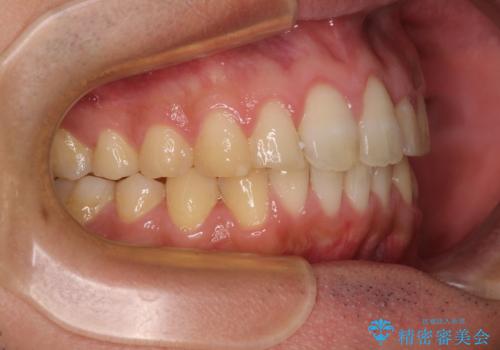

捻れて飛び出した前歯 インビザラインで整った前歯に

- 上下前歯のデコボコと、それに伴う出っ歯を気にして来院された患者様です。

インビザラインによる上下歯列の側方拡大と後方移動、IPR(歯と歯の間を削る)にるスペースの獲得により歯列を整えることとしました。

歯と歯の間を削ることでうまくスペースコントロールでき、また、毎日22時間以上しっかりとマウスピースを装着していただいたので、スムーズに治療が進みました。